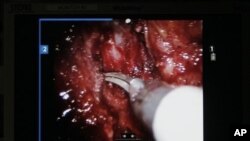

Por, krahë robotikë kryejnë një operacion delikat në rrugët urinare të pacientit.

Krahët robotikë bëjnë pjesën më të madhe të punës, ndërsa kirurgu kryesor përdor leva për t’i kontrolluar dhe drejtuar ato.

Ndërsa krahët robotikë të përdorur në këtë procedurë kanë një gamë lëvizjeje të tillë që bën të mundur që instrumente kirurgjikale mjaft të vogla të kryejnë operacione të ndërlikuara te fëmijët.

Pajisja e ndihmuar nga roboti, e zhvilluar nga CMR Surgical Ltd me bazë në Kembrixh, synon të arrijë një saktësi që njeriu nuk e arrin dot, nëpërmjet përdorimit të instrumenteve të vogla kirurgjikale, kontrollit të robotit, si dhe një ekrani të zmadhuar me rezolucion të lartë.

“Ndërhyrja kontrollohet nga kirurgu, gjithsesi. Duket sikur ndihma robotike është e atomatizuar, por në fakt kontrollohet nga kirurgu”, thotë kirurgu Ewan Brownlee